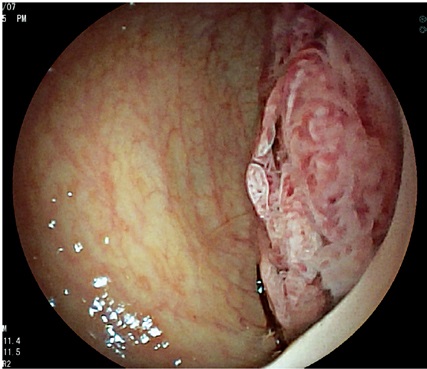

Se encontró defecto de los esfínteres en 40 pacientes (29,41%), de los cuales 6 fueron hombres y 34 mujeres; aquí cabe anotar que el 93,33% (n =28) de las mujeres que tienen historia de incontinencia, también tienen antecedente de desgarro. De las 34 mujeres con defectos en los esfínteres, 32 lo tuvieron localizado en canal anal medio, con compromiso en nivel anterior, 1 de ellas con atrofia difusa de esfínteres, y otra con compromiso de canal anal inferior (figura 2).

Por otro lado, en el grupo masculino con estudio por incontinencia, el diagnóstico en todos fue cambios por atrofia del aparato esfinteriano, que pudo verse en cualquiera de las localizaciones del canal anal y que se evidenció como engrosamiento de los músculos en general y cambios difusos de la ecogenicidad de los mismos, sin posibilidad de determinar el borde que los delimita. Se encontró fístula perianal en 16 pacientes (11,8%); la principal forma de presentación de las fístulas fue transesfintérica (37,5%), seguida por las interesfintéricas y anovaginales (figuras 3 y 4). Doce pacientes presentaron absceso perianal (8,8%); de estos, el 83% correspondió a abscesos submucosos o isquiorrectales (figura 5).

Los demás diagnósticos finales se presentan en la tabla 4. Es de resaltar que se pudo determinar en el grupo diagnosticado como neoplasia benigna de recto, la posibilidad de resección endoscópica en lesiones que tenían planeadas cirugías más invasivas (figura 6 y 7), así como la posibilidad de determinar la recuperación del aparato esfinteriano en 3 pacientes en seguimiento por cáncer de canal anal después de manejo por parte de oncología. En 2 pacientes de los diagnosticados con neoplasia maligna de recto se identificó lesión menor a T2 y N0 según las clasificación de TNM (figura 8), considerándose lesiones tempranas; en el otro 88,8% se encontraron lesiones avanzadas (figura 9 y 10). También se anota que, dentro de la categoría otros, están con orden de frecuencia de mayor a menor endometriosis o endometrioma, enterocele, fisura anal, várices rectales y un caso de cáncer de colon sigmoides.